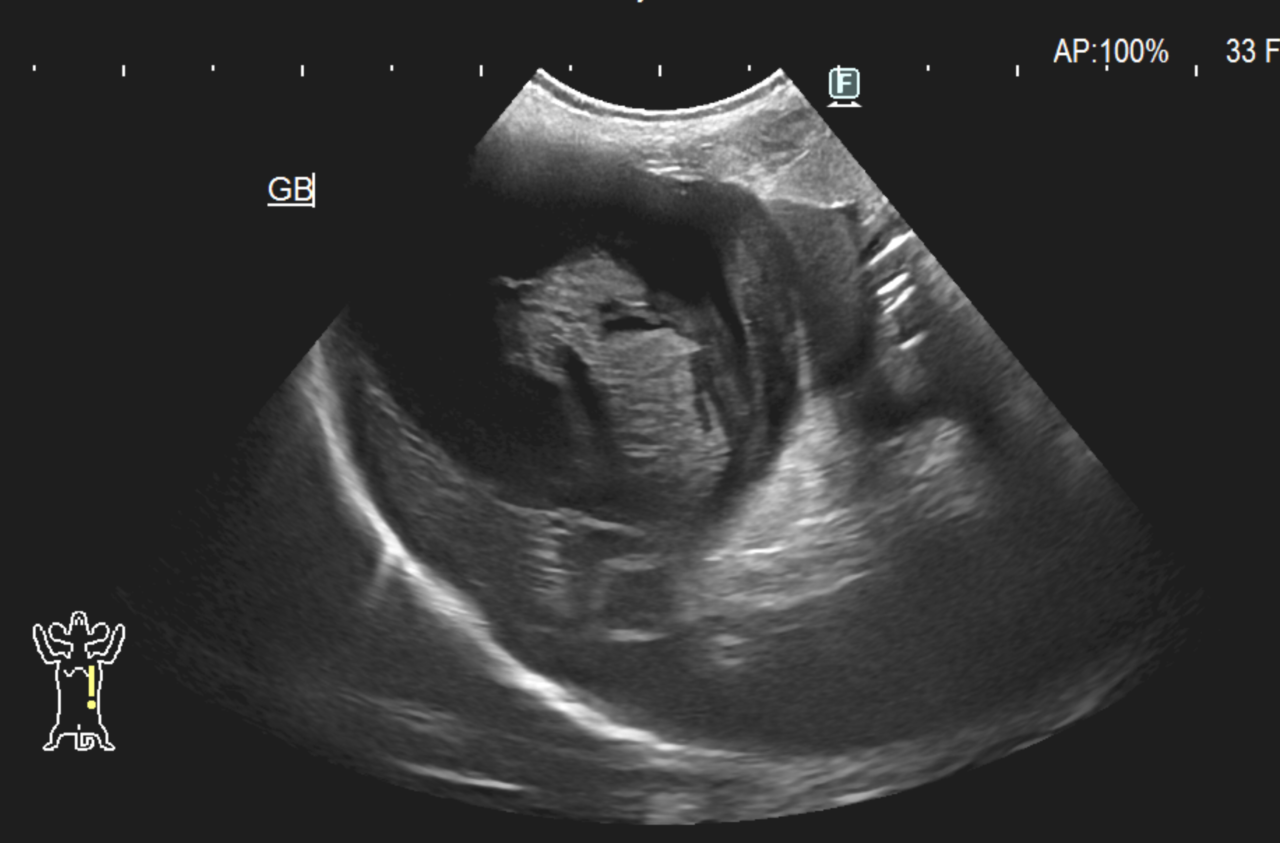

高齢のプードルさんの胆嚢破裂による胆汁性腹膜炎の緊急治療依頼がありました。胆嚢粘液嚢腫を扱う場合には、血液の希釈をできるだけ避け、吸入麻酔による低血圧への対応が必要です。また敗血症やアシドーシスにも十分注意する必要があります。術後の数日間はクリティカルな状態が続きましたが、頑張って乗り越えてくれました。胆嚢は症状をなかなか表さず、沈黙の臓器と言われています。小型犬ではこの病気が多くみられるので定期的にエコーでの検診をお勧めします。